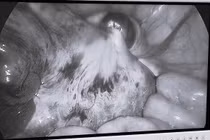

Mới đây, các bác sĩ BVĐK tỉnh Tuyên Quang vừa mổ nội soi, tháo xoắn bảo tồn thành công phần phụ (gốm buồng trứng và vòi tử cung) cho một bé gái 5 tuổi ở TP Tuyên Quang.

Chỉ đau bụng quanh rốn, trẻ đi khám phát hiện xoắn buồng trứng và vòi tử cung. May mắn trẻ đến sớm mổ nội soi, tháo xoắn, bảo tồn thành công phần phụ (gồm buồng trứng và vòi tử cung).

Bệnh viện Đa khoa TP.Cần Thơ cho biết, các bác sĩ vừa phẫu thuật cấp cứu tháo xoắn phần phụ phải, bóc u giúp bảo tồn tai vòi, buồng trứng cho bệnh nhi 15 tuổi có tiền sử sốc thuốc mê, dị ứng với nhiều loại thuốc mê, kháng sinh.